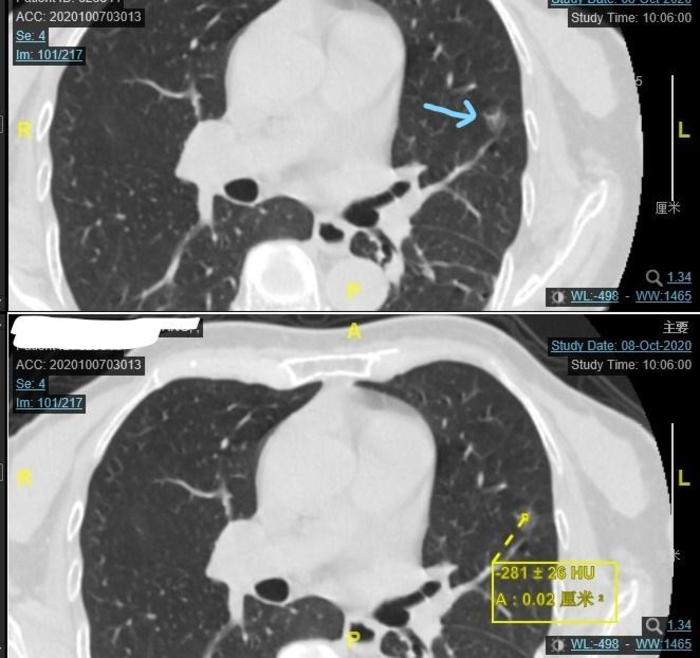

上图为今年9月份住院后的CT,由两张CT组成。上面的CT的蓝色 箭头指向的是左上肺实性结节。下面的CT黄色箭头指向的是这个结节紧贴斜裂,好像比两年半前大了1毫米,差别不大。

上图为今年9月份住院后的CT,由两张CT组成。上面的CT的蓝色 箭头指向的是左上肺混合磨玻璃结节。下面的CT黄色方框是这个结节的最高CT值-281,大小与两年半前比变化不大。应该是一个早期肺癌。